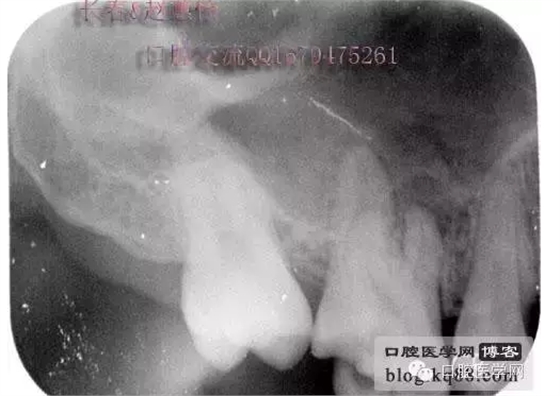

這個是術前照片,一切如常

患牙是死髓牙,患者是一位大學生,探查根管時一切都很順利,就有點忽視了,當然這個臺階是人為造成的,造成的原因呢就是使用機擴時跳號了,所以大家一定要逐號使用啊,預備出一個臺階,后續(xù)要搭上很長時間才能搞定,好不容易越過臺階下去的銼,一提拉出來就下不去了,著實讓人郁悶,一切都要從頭再來,這個時候再下銼的時候就必須預彎了。而且要多角度試探,很是考驗耐心的時候。吃一塹長一智嘛!